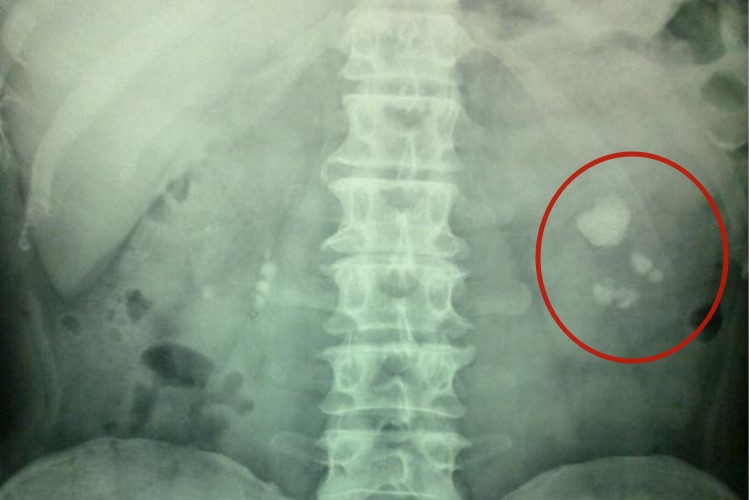

肾结石

肾结石患者主要表现为脊肋角、腰部和腹部等处出现阵发性的疼痛,并向下腹部及会阴部放射;疼痛可分为钝痛和绞痛,严重者呈刀割样痛,同时伴有恶心、呕吐、血尿、脓尿等症状,若肾结石引起梗阻可引起无尿。